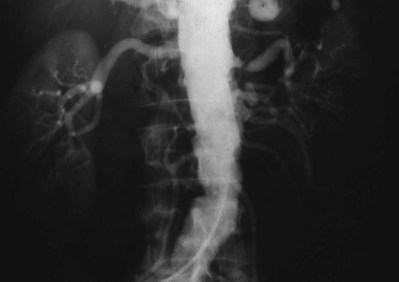

Intrarenal aneurysms are considered congenital and account for one fifth of aneurysmal disease affecting the kidney (Fig. 54–47). In some instances they may develop secondary to atherosclerosis, mural dysplasia, trauma, inflammation (arteritis), or needle biopsy. Intervention is warranted for lesions larger than 2 cm or those associated with hypertension. Lesions can rupture and dissect leading to ischemia or may contribute to thrombus formation and warrant intervention (revascularization or coil placement). Women in childbearing age with evidence of aneurysms are urged to undergo repair secondary to risk of rupture and associated high rates of maternal and fetal mortality (Figs. 54-48 and 54-49) (Yang and Hye, 1996; Centenera et al, 1998).

Figure 54–47 A, Large left congenital renal aneurysm and arteriovenous malformation. B, Note early filling of the renal vein and inferior vena cava.